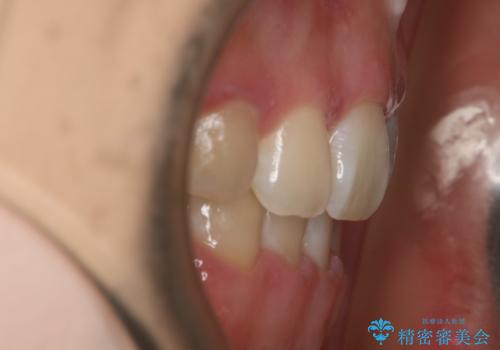

ワイヤー矯正の中でも、上顎を裏側・下顎を表側に装置をつけて動かす方法をハーフリンガルといいます。

ハーフリンガルを選択すると、ワイヤー矯正の利点である抜歯ケースへの対応が可能な点と、表側の装置の欠点である装置が目立つという点をカバーして矯正治療を進めることができます。

表側の装置と違い、使えるワイヤーの種類に制限があり平均治療期間が長くなりやすい点、装置の作製自体の金額が掛かることから費用面で表側装置よりも高額になるという点はマイナスポイントであるといえますが、しっかりと口元を下げたり、噛み合わせの構築を行うことは遜色なく行えるため人気のある装置となっております。